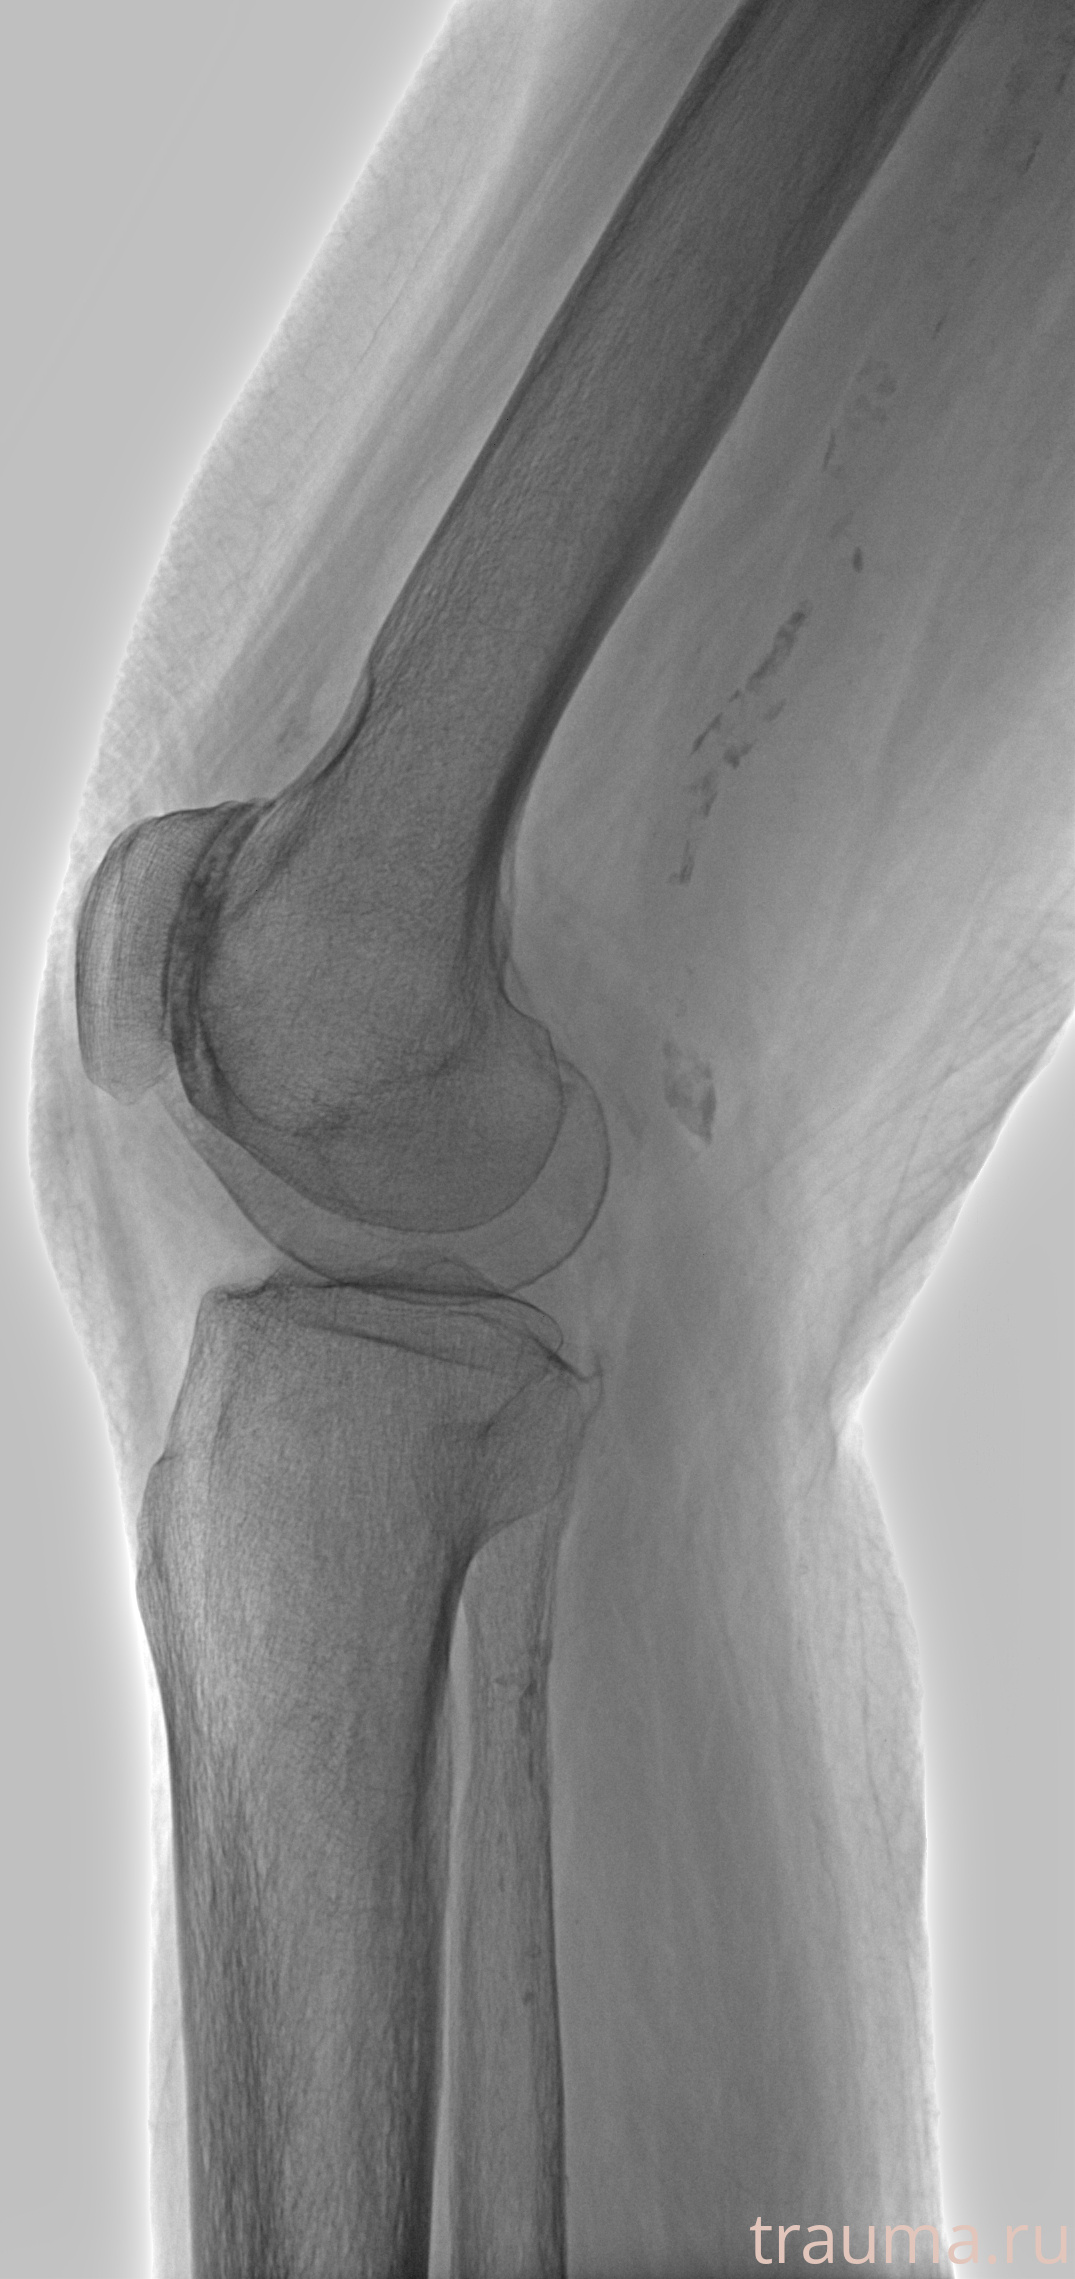

Рентгенограммы

Рентген на дому: по вашему адресу приезжает врач-рентгенолог, травматолог-ортопед с мобильным рентгеновским аппаратом, проводит диагностику травмы или заболевания, делает необходимые рентгенограммы, дает рекомендации по дальнейшему лечению. Получить качественные снимки в домашних условиях возможно благодаря уникальной методике, разработанной МосРентген Центром для института  Склифосовского